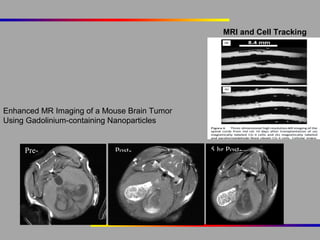

MRI and Cell Tracking

Enhanced MR Imaging of a Mouse Brain Tumor

Using Gadolinium-containing Nanoparticles

Pre-

cont

rast

Postcontrast

5 hr Postcontrast